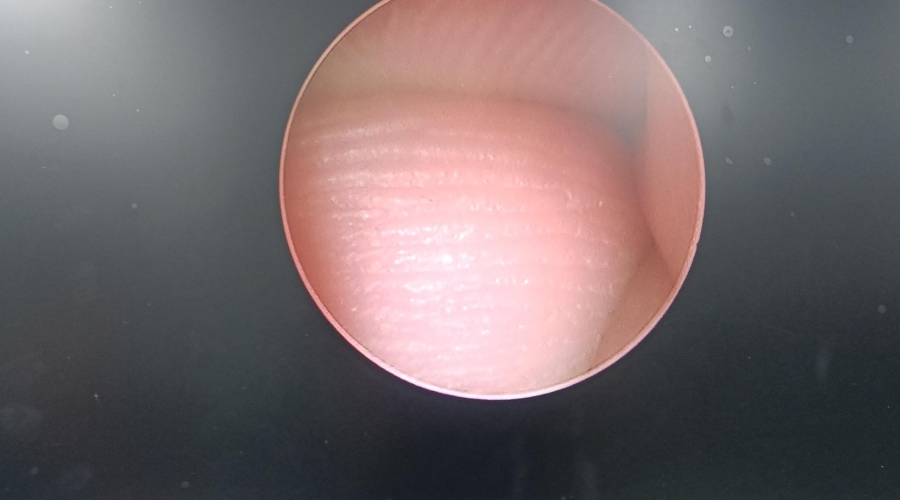

以下為維修案例分析及故障實拍:

| 設備型號 | YOUSHI宮腔一體鏡 Y2052 |

| 故障內容 | 圖像模糊,棒透鏡破碎。 |

| 維修方案 | 更換棒透鏡 ,校對圖像,內窺鏡抗震蕩抗沖擊性能測試,內窺鏡密封性性能檢測;內窺鏡抗震蕩性能測試,內窺鏡冷熱沖擊性能檢測。 |